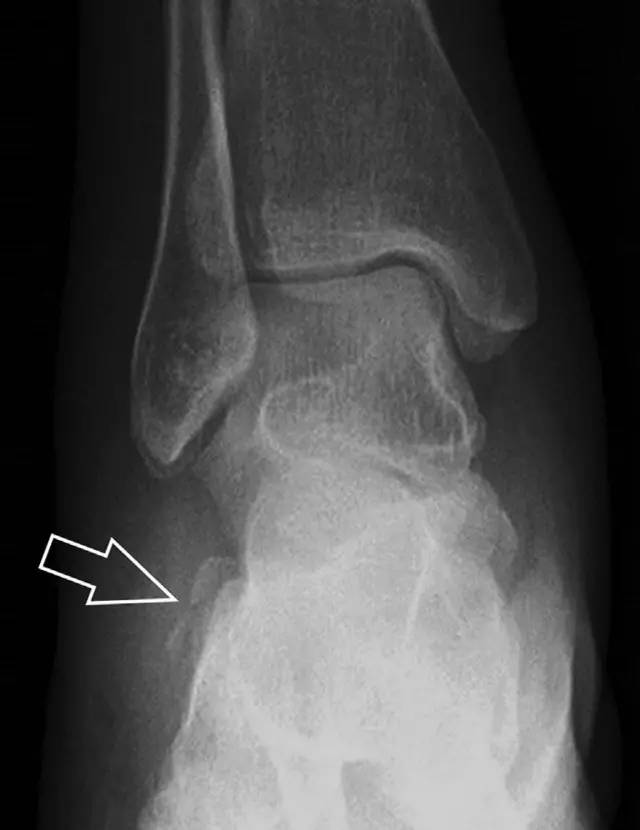

21趾短伸肌跟骨撕脱性骨折

另一种重要的跟骨撕脱性骨折,于足内翻时发生在趾短伸肌的起点处。观察来自跟骨背外侧的、不同大小的骨折块,前后位 X 片最适合不过了(图 7)。

图 7 溜冰受伤的患者,趾短伸肌跟骨撕脱性骨折。正位片示 2 个骨折块(箭头)来源于跟骨前外侧、趾短伸肌的起点处。踝关节外侧远端是否存在软组织水肿是一个重点观察点